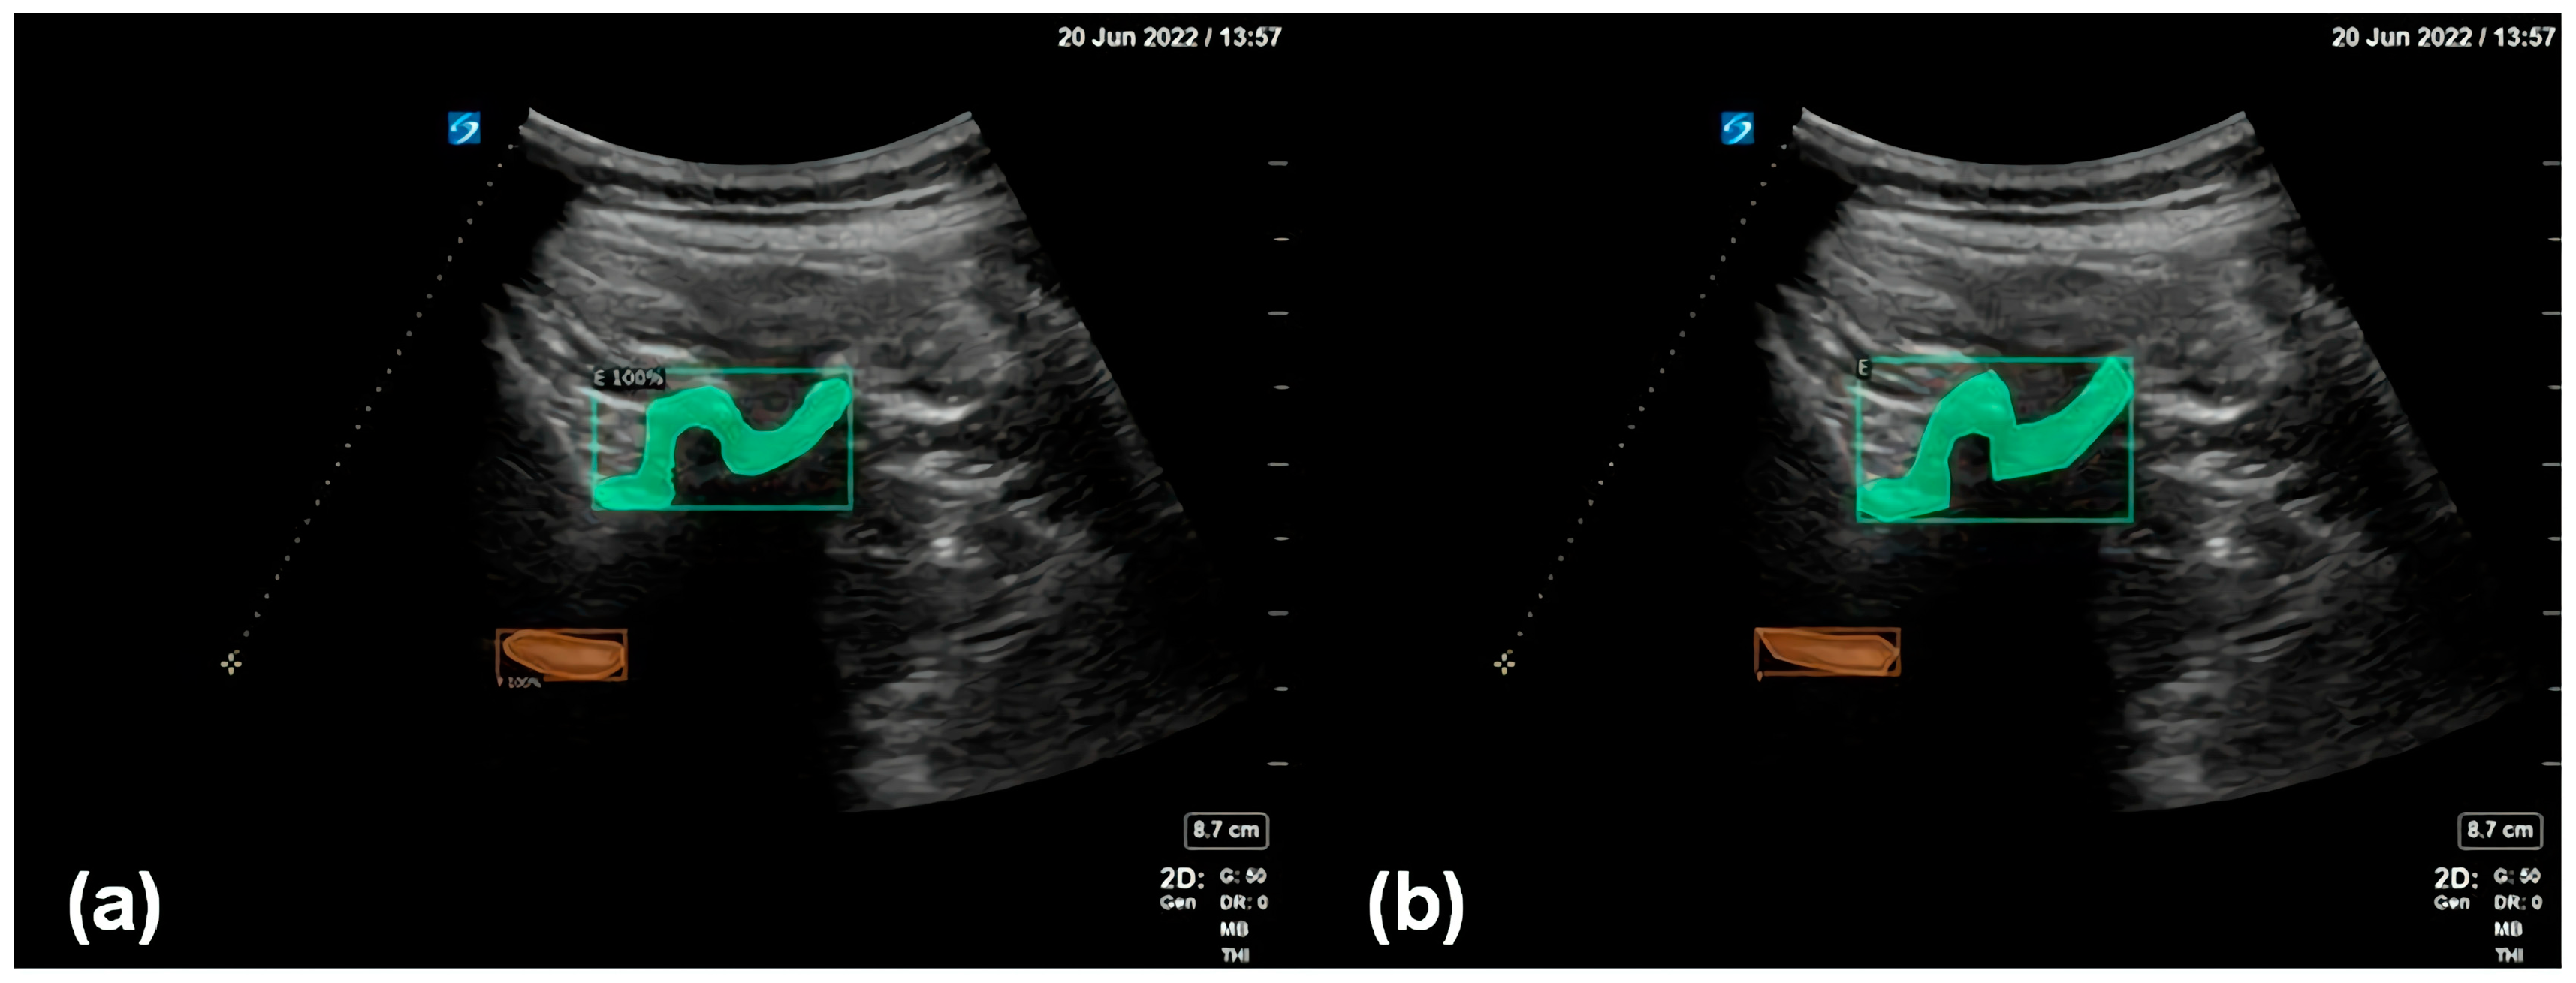

In Figure 5, the green area is the inspected and segmented facet joint structure, and the orange area is the inspected and segmented ventral complex. The figure shows that the results for the facet joint structures inspected and segmented using the proposed method are close to the results of manual annotations by human experts, indicating the good performance of the enhanced data annotation method and the deep learning model adopted in this work.

Figure 5. (a) Detection and segmentation of the facet joint (green) and the ventral complex (orange) using the proposed method. (b) The facet joint (green) and the ventral complex (orange) as manually annotated by human experts.